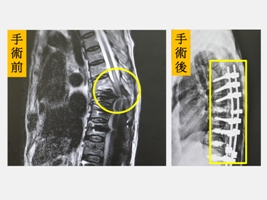

台中一位77歲的陳老太太之前因為退化性脊椎側彎併脊椎狹窄症接受脊椎矯正、減壓和固定融合手術,手術後恢復得不錯,很快就回到正常生活。陳老太太有一天在家整理盆栽搬動花盆時突然背部一陣劇痛,下半身突然無力跌坐在地上,兩個下肢癱瘓無力,家人趕緊將她送到仁愛長庚合作聯盟醫院(大里仁愛醫院)的急診室。急診醫師發現陳老太太的大小腿癱瘓無力,只剩腳踝可微動,經過緊急核磁共振攝影檢查顯示第七胸椎發生爆裂性骨折,而且壓迫到脊髓,立即聯絡脊椎中心陳盈佑主任安排緊急手術,隔天其大腿開始有微微移動。陳老太太除了接受骨質疏鬆症的治療之外,在疼痛減輕後,復健科醫師安排復健療程積極訓練,約一個月後已經可以持著四腳助行器慢慢行走,逐漸提升生活品質。